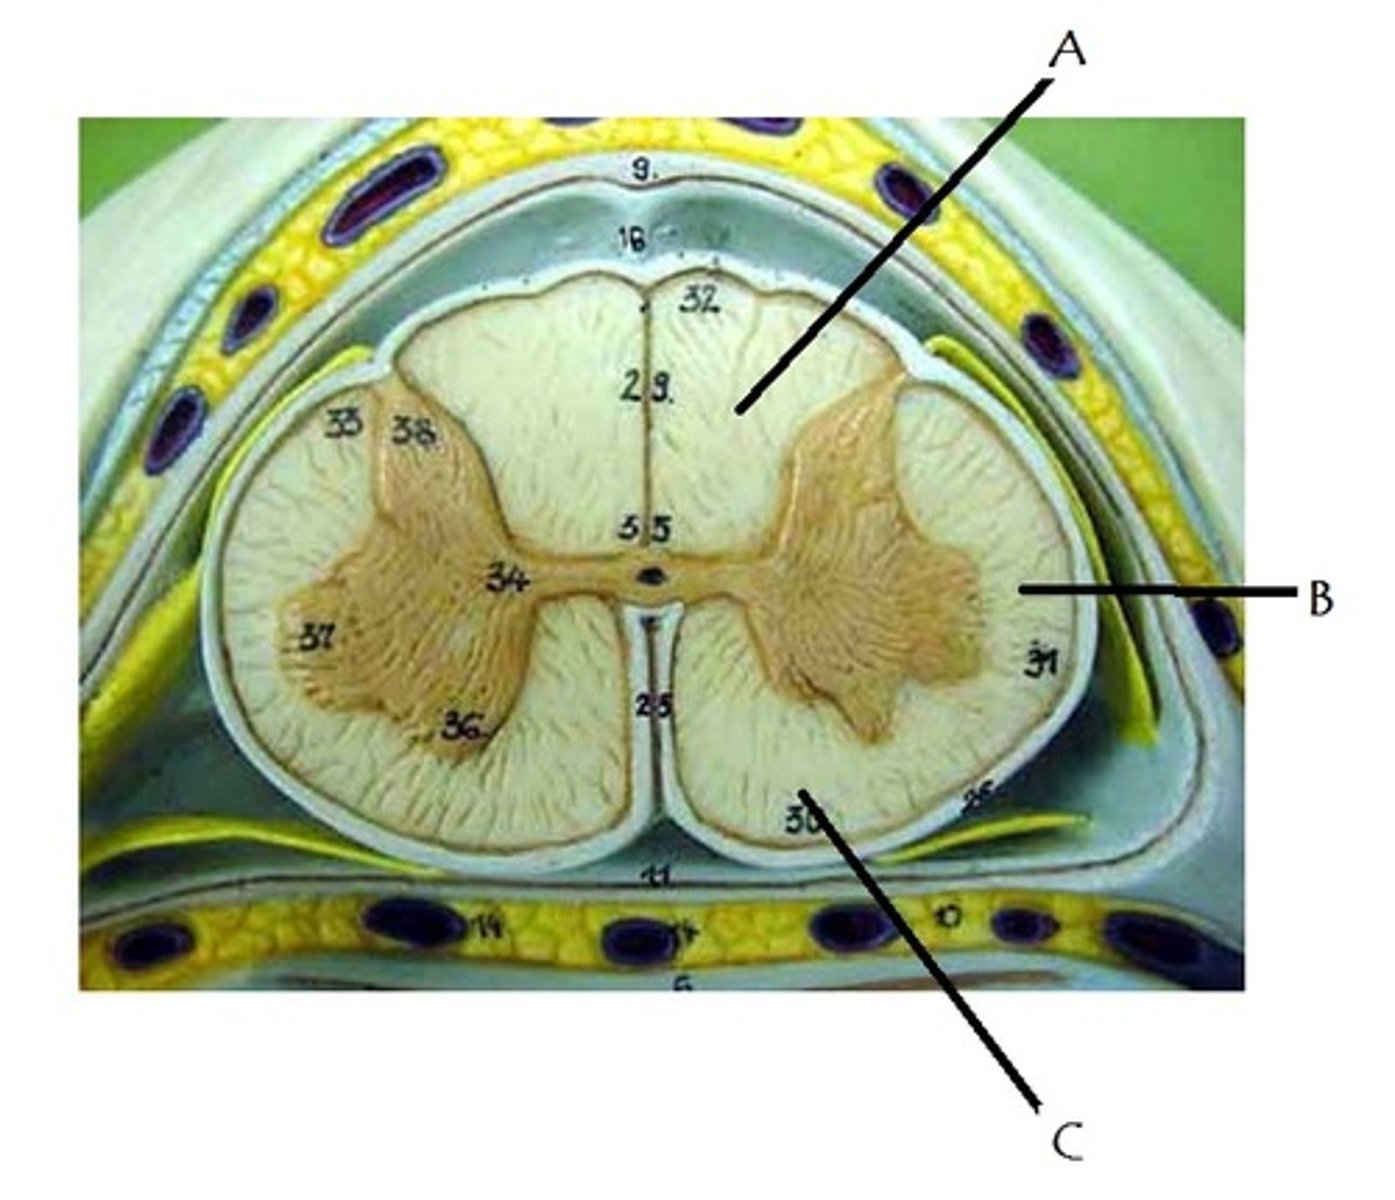

What is the area labelled A called?

subarachnoid space

What is the area labelled B called?

central canal

What is the area labelled C called?